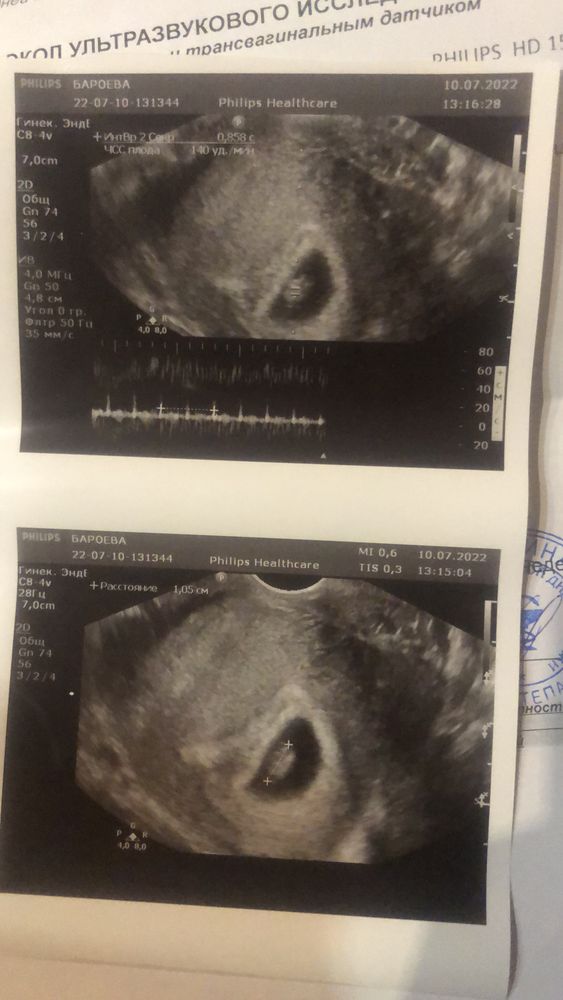

Приключения гороха (узи в 6,1 и 7,2)

Поздравляю!! Лёгкой б и родов в срок!! У меня жт в 4.6 было 16. Я так плакала, в 6.2 уже 18, больше не ходила на узи, надеюсь подросло и все норм. Токс тоже не отпускает, особенно по вечерам.